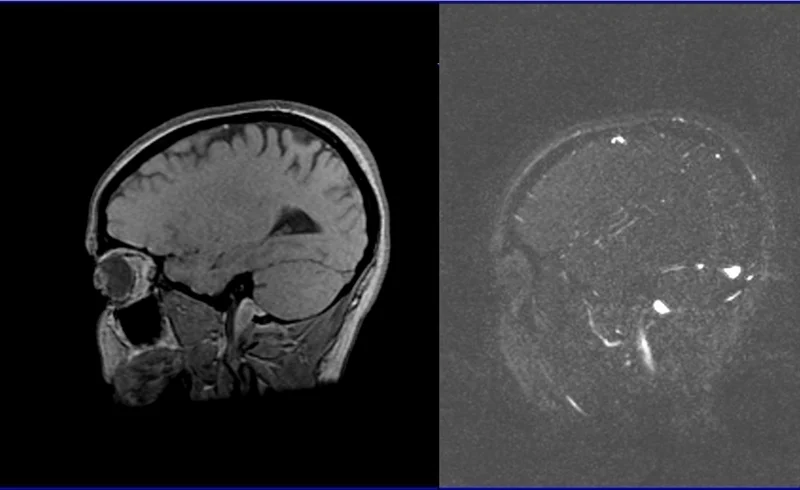

Susceptibility weighted imaging (SWI)